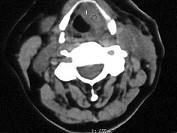

问题 女、54岁,鼻咽部异物感约三个月,PE:左侧声带固定,可见肿物,CT如图所示,应诊断为()

选项 A.喉部乳头状瘤 B.喉癌 C.喉部血管瘤 D.慢性增生性喉炎 E.增生型喉结核

答案 B